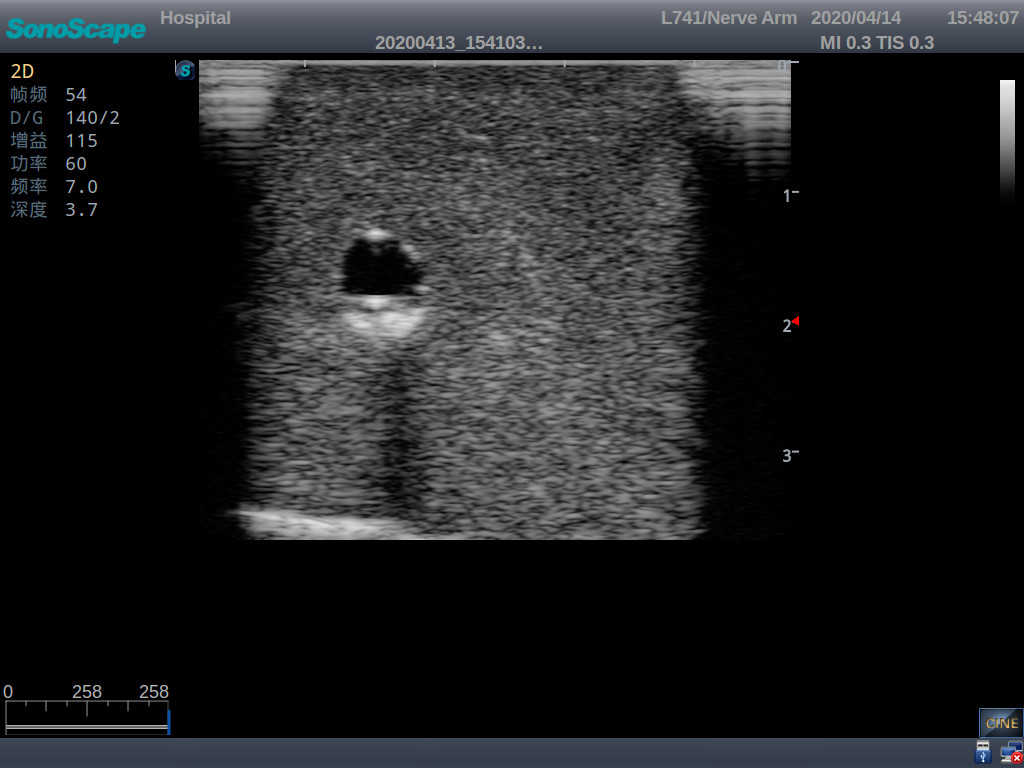

2) It can be used by real ultrasound machines

3) Clear and real images of the tissues and organs (basilic vein and superior vena cava)